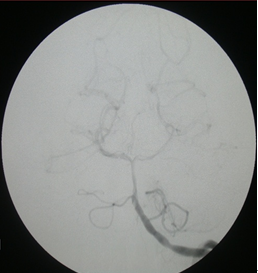

4:17 DSA脑血管造影示基底动脉闭塞。(图二)

图二:治疗前DSA示基底动脉闭塞